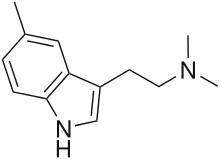

| 5-Methyl-DMT (5,N,N-TMT) | artificial | 5-CH3 | CH3 | CH3 | 5,N,N-trimethyltryptamine | 22120-39-4 |

5-Methyl-αET | 1-(5-methyl-1H-indol-3-yl)butan-2-amine | 1380148-21-9 |